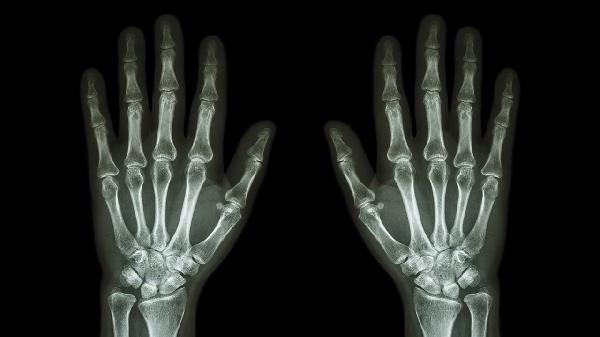

尿酸高确实可能导致手指关节疼痛。这个问题主要源于尿酸在体内过多积累,形成尿酸盐结晶,这些结晶沉积在关节中,诱发局部炎症反应。手指关节因此可能出现红、肿、热、痛等症状。其实,不仅是手指关节,其他如脚趾、足背、膝关节等部位也可能受到影响,出现类似的不适。

1、尿酸结晶的形成:当尿酸水平过高时,尿酸盐结晶容易在关节内沉积。这些微小的结晶会刺激关节,导致炎症和疼痛。想象一下,像是细小的砂砾进入了精密的机械装置,摩擦和刺激会引发一系列不适。